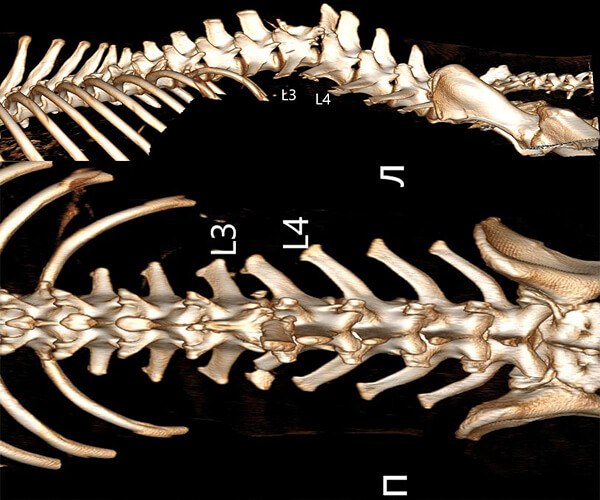

Сейчас в теле щенка застряли пули, повреждён позвоночник и спинной мозг. Он не может лечь, ест и спит только сидя, и каждую минуту терпит боль.

Врачи говорят, что полностью восстановить чувствительность уже не получится. Но у Зухрая есть шанс облегчить страдания и прожить жизнь без постоянной боли. Для этого нужны обследования и лечение в Москве.